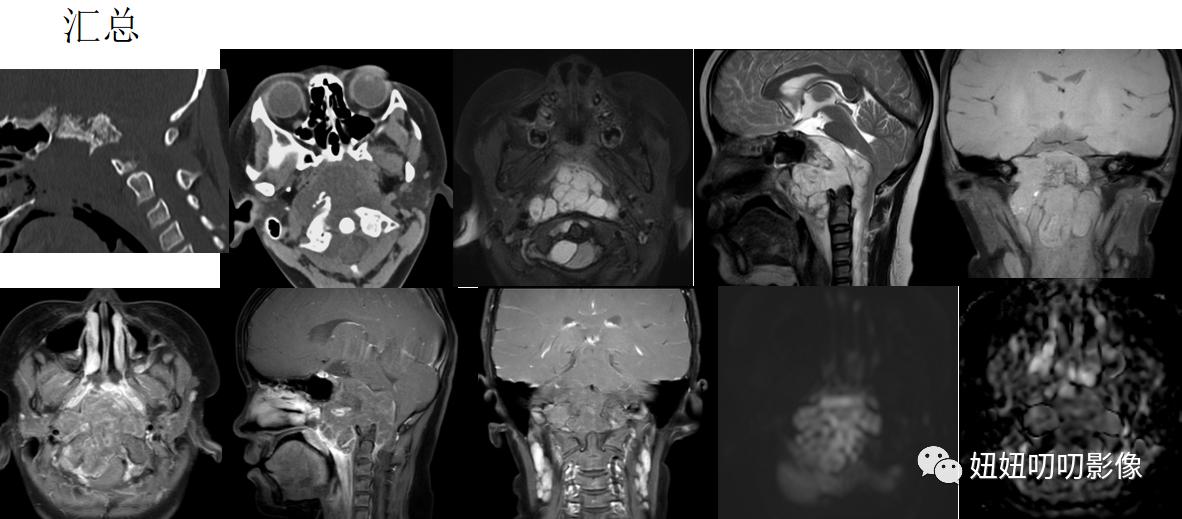

CT:鼻咽、口咽部后壁见一低密度软组织肿块,CT值约29Hu,边界不清,大小约5.8x4.6x6.1cm,内见斑片状高密度灶,包绕枕骨斜坡及右侧岩锥、右侧枕骨,骨质不同程度破坏。双侧咽隐窝、显示不清,病灶向鼻咽、口咽腔内凸出。双侧上颌窦、筛窦、蝶窦、额窦气化良好,窦腔显示清晰,未见明显粘膜增厚。

斜坡区见大小约5.6×5.7×6.1cm之不规则长短T1、长短T2信号肿块,其内见T2低信号分隔,DWI呈不均匀高信号,ADC图呈等低信号,增强呈明显不均匀强化,斜坡、枕骨骨质不同程度破坏,肿块向前凸向鼻咽口咽部,并推压斜坡-椎前软组织及双侧下鼻甲后部,局部增厚FS-T2WI呈稍高信号,双侧咽隐窝显示不清,向后压迫桥池及脑干延髓后方脑组织,第四脑室受压变扁,小脑扁桃体变尖下移,紧贴右侧听神经,部分包绕椎-基底动脉。

CT:鼻咽、口咽后壁巨大软组织肿块,枕骨斜坡、右侧岩锥、右侧枕骨骨质破坏;符合恶性肿瘤CT表现。建议MR检查。

MRI:斜坡区异常信号灶,符合脊索瘤MRI表现,请结合临床及病理学检查。

①:第病理:脊索瘤;

②:颅底脊索瘤较骶椎脊索瘤发病年轻约10岁,30-50岁为好发年龄;脊索瘤生长缓慢,手术切除局部复发率高;

③:脊索瘤无硬化边,强化轻中度,沙砾感,蜂窝状。